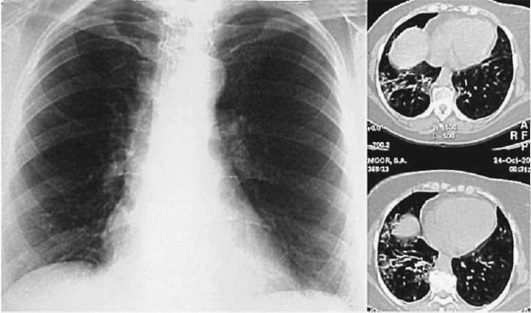

Лучевые методы исследования. Рентгенологическая картина при ЭТА зависит от стадии заболевания. В начальной фазе выявляются признаки отека интерстициальной ткани легких и распространенные мелкоочаговые затенения. При прогрессировании процесса формируются двусторонние изменения легочного рисунка по типу интерстициального фиброза, преимущественно в нижних отделах легких (рис. 2.28). В далеко зашедших случаях определяется мелко- и крупноячеистая деформация легочного рисунка. Описаны случаи, когда единственным рентгенологическим признаком болезни был односторонний плевральный выпот. Отсутствие каких-либо изменений на рентгенограммах отнюдь не исключает ЭТА. Так, при бериллиозе у 23-59% больных может выявляться умеренно выраженная двусторонняя лимфоаденопатия, а в ряде случаев - рентгенотрицательная форма бериллиоза (Dweik R.A., 2015). У 30% из 71 больных ЭТА, наблюдавшихся нами в клинике пульмонологии, в момент обследования изменений на рентгенограммах не было (Орлова Г.П., 2019). Группа больных ЭТА была обозначена условно как рентгенотрицательная группа. Уточнить диагноз помогает КТ легких, выявляющая интерстициальные изменения в легочной ткани по типу «матового стекла», усиление и деформацию легочного и сосудистого рисунка (рис. 2.29), фиброзные изменения тяжистого и звездчатого типов, на поздних стадиях - «сотовое легкое». ВРКТ выявляет «матовое стекло» и другие изменения в легочной паренхиме, которые не видны при обычном рентгенологическом исследовании. Но даже ВРКТ не всегда выявляет изменения в легочной ткани. Так, в 25% случаев гистологически подтвержденного хронического берил-лиоза легких ВРКТ была нормальной (Dweik R.A., 2013; Амосов В.И., Сперанская А.А., 2015; Amanullah S. et al., 2015).

Рентгенологические изменения в легких при ингаляционных лихорадках также могут отсутствовать или проявляться в виде летучих инфильтратов (Ahsan S.A. et al., 2009; Shimizu T. et al., 2012; Greenberg M.I. et al., 2015). При бериллиозе, помимо диффузных инфильтратов и усиления легочного рисунка, за счет интерстициального компонента у 23-59% больных может выявляться лимфаденопатия (Sirajuddin A. et al., 2009).

Проведенное нами динамическое исследование КТ-паттернов у 42 больных ЭТА показало трансформацию отдельных типов интерстициальных пневмоний по мере прогрессирования патологического процесса в фиброзную НСИП или ОИП (рис. 2.30), что подтверждает объединительную концепцию интерстициальных пневмоний вне зависимости от этиологического фактора, которые являются не отдельными нозологическими формами, а стадиями течения фиброзирующего процесса в легких (Илькович М.М., Новикова Л.Н., 2018; Орлова Г.П. и др., 2019).